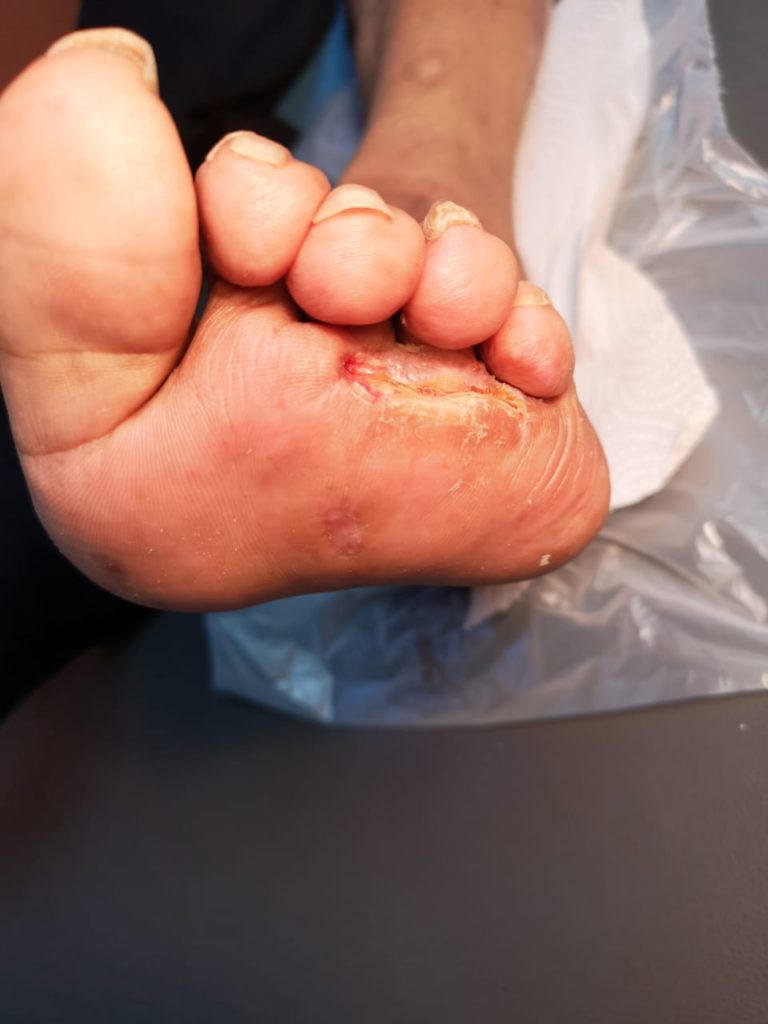

Caso de pie diabético infectado y ulcerado, al inicio y luego de tratamiento…